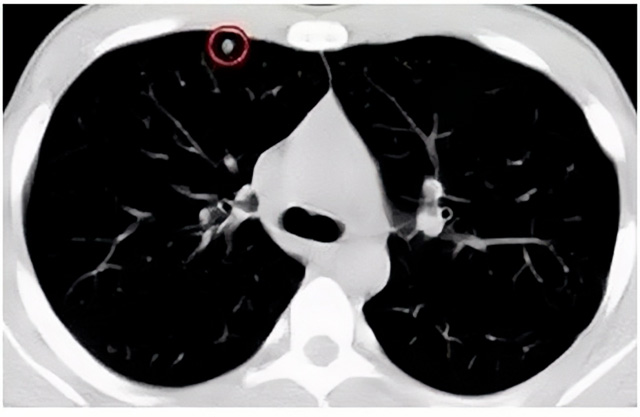

移動(dòng)CT體檢車可以檢查肺結(jié)節(jié)發(fā)現(xiàn)早期肺癌

移動(dòng)CT體檢車可以做肺部檢查。隨著多層螺旋CT肺部低劑量掃描的臨床應(yīng)用,目前很多人選擇肺部CT作為常規(guī)檢查項(xiàng)目,較大地提高了肺結(jié)節(jié)的檢出率。如果檢查發(fā)現(xiàn)肺部有肺結(jié)節(jié)是磨玻璃型的,小于5mm的微小結(jié)節(jié),大部分都是良性的。如果達(dá)到1CM以上的,很有可能有肺癌的機(jī)率。根據(jù)其內(nèi)密度不同可分為磨玻璃結(jié)節(jié)、實(shí)性結(jié)節(jié)、部分實(shí)性結(jié)節(jié)。根據(jù)其大小可分為肺大結(jié)節(jié)、小結(jié)節(jié)和微小結(jié)節(jié)。如果是炎癥性肺結(jié)節(jié),幾個(gè)月后復(fù)查有變化變小就不用做手術(shù)。如果CT再次復(fù)查結(jié)節(jié)沒(méi)有變化,沒(méi)有縮小就需要升級(jí)做病例檢查。病理檢查的確診性是最高的。是有沒(méi)患癌的標(biāo)準(zhǔn)。檢查發(fā)現(xiàn)早的話,規(guī)范手術(shù)治療,手術(shù)后5年的存活率很高的。肺癌這個(gè)要早發(fā)現(xiàn)早治療。

現(xiàn)在的移動(dòng)CT體檢車的分辨率比X光高,CT掃描的圖像越來(lái)越薄顯像更清晰,檢查更準(zhǔn)確。得到了普及,肺結(jié)節(jié)的測(cè)出率很高的。但是顯浩告訴大家,肺結(jié)節(jié)不等于肺癌。雖然很多是良性,但是很多肺癌都是肺結(jié)節(jié)發(fā)展來(lái)的。 必須定期檢查復(fù)查。磨玻璃結(jié)節(jié),肺癌的機(jī)率較高。肺癌是惡性腫瘤病死率最高的。除了環(huán)境,遺傳,等因素。吸煙,從事煙霧工作行業(yè)的人員比較危險(xiǎn)。發(fā)病比例高。肺部疾病早發(fā)現(xiàn)早治療,依舊是肺部疾病的治療標(biāo)準(zhǔn)。

一旦CT檢查發(fā)現(xiàn)肺結(jié)節(jié),若不規(guī)律復(fù)查,檢查等同于白檢。所以在復(fù)查中,如果結(jié)節(jié)中發(fā)現(xiàn)有增大的趨勢(shì),或大小發(fā)生了變化,我們必須提請(qǐng)注意及時(shí)治療,不要掉以輕心。移動(dòng)CT體檢車的普及化,讓肺部檢查更準(zhǔn)確更高效。發(fā)現(xiàn)肺結(jié)節(jié)時(shí),及時(shí)就醫(yī)并進(jìn)行專業(yè)評(píng)估是確保準(zhǔn)確分類和采取適當(dāng)措施的關(guān)鍵。